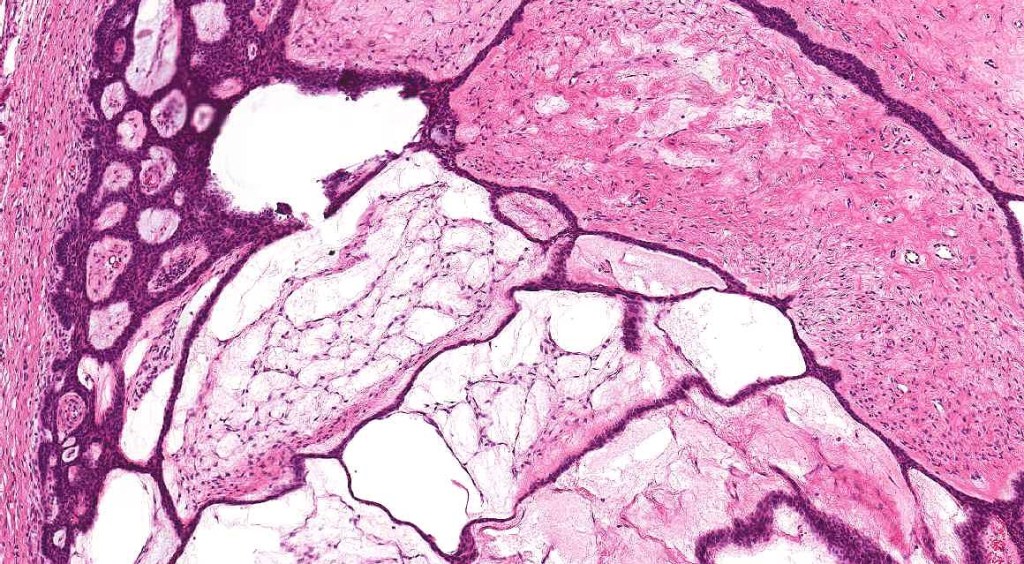

Histological features

•Anastomosing basaloid, narrow epithelial strands associated with a prominent fibrous (sometimes myxoid) stroma

•Ductal differentiation likely represents entrapped ducts rather than spread along the eccrine ducts

•Peripheral palisade

•Retraction artifact variably present

•Occasional cysts